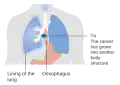

Staging

Staging is based on the TNM staging system, which classifies the amount of tumor invasion (T), involvement of lymph nodes (N), and distant metastasis (M).[16] The currently preferred classification is the 2010 AJCC staging system for cancer of the esophagus and the esophagogastric junction.[16] To help guide clinical decision making, this system also incorporates information on cell type (ESCC, EAC, etc.), grade (degree of differentiation – an indication of the biological aggressiveness of the cancer cells), and tumor location (upper, middle, lower, or junctional[46]).[47]

-

T1, T2, and T3 stages of esophageal cancer -

Stage T4 esophageal cancer -

Esophageal cancer with spread to lymph nodes